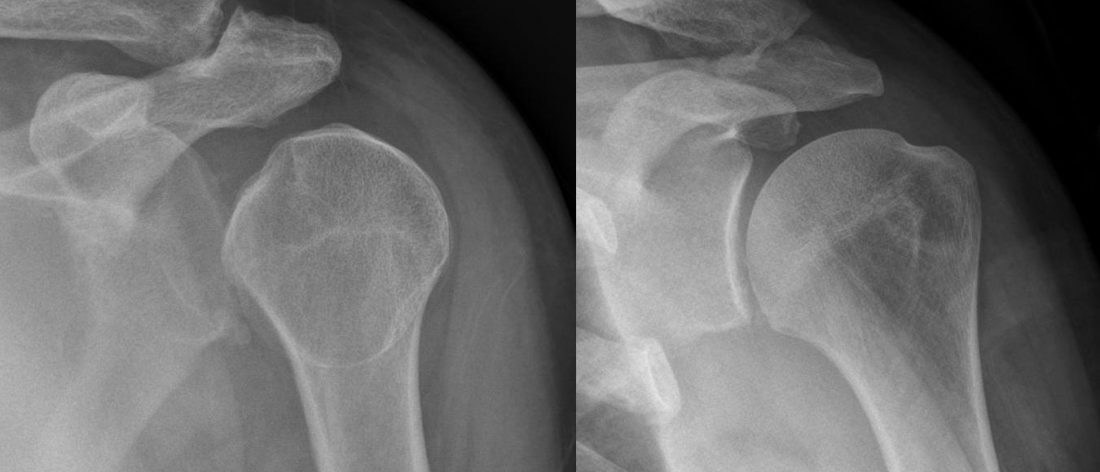

Dislocated shoulder

The shoulders are especially prone to dislocation injuries. Fingers, hips, ankles, elbows, jaws and even the spine can be dislocated as well. A dislocated vertebrae in the spine often damages the spinal cord and can paralyze body parts lower than the injury site.